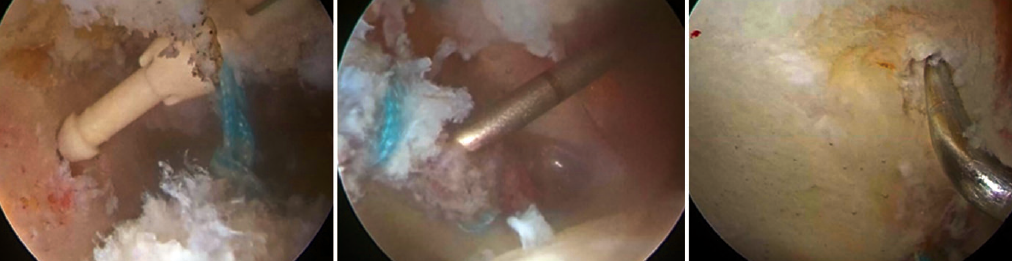

Repair of the labral lesion was made with two knotless PEEK anchors measuring 2.8 mm (PopLok® Knotless Suture Anchor, ConMed Corp., New York, USA) and a 1.3 mm knotted anchor (Y-Knot® Flex, ConMed Corp., New York, USA). Microperforations were made in the grade II acetabular chondral lesion, measuring 1.0 × 1.0 cm2 (Figure 4).

After treatment of the concomitant disorders, the femoral head lesion was visually identified and the absence of femoral head collapse at the site of necrosis was checked arthroscopically (Figure 6).

Six perforations were made with the guide of the 1.3 mm anchors (Y-Knot® Flex) and three perforations were made with the guide of the 2.8 mm knotless PEEK anchors (PopLok® Knotless Suture Anchor) for CD of the femoral head through the anterolateral region of the femoral neck under visual guidance, establishing a separation of 3 mm between them, with a diameter of 1.3 mm and 2.8 mm, respectively, and checking bleeding of each perforation (Figure 7 and Video 1).

Placement of the autologous stem cells

Aspiration of the irrigation solution was performed. By means of a perforation made with the guide of the 2.8 mm knotless PEEK anchors (PopLok® Knotless Suture Anchor), measuring 2.8 mm in diameter, the previously harvested autologous stem cells were placed under visual control. Lastly, capsule closure was carried out using high resistance sutures, with sealing of the portals. The total duration of surgery was three hours and 15 minutes; one hour and 30 minutes with traction of the lower extremity (Figure 8).

Figure 3. Arthroscopic acetabuloplasty using the over-the-top technique. Control of the procedure with image intensifier.

Figure 4. Labral repair with anchorings, affording adequate stabilization checked through palpation and performing microperforations in the chondral lesion.

Figure 7. Core decompression of the femur through microperforations; arthroscopic view and fluoroscopic control.